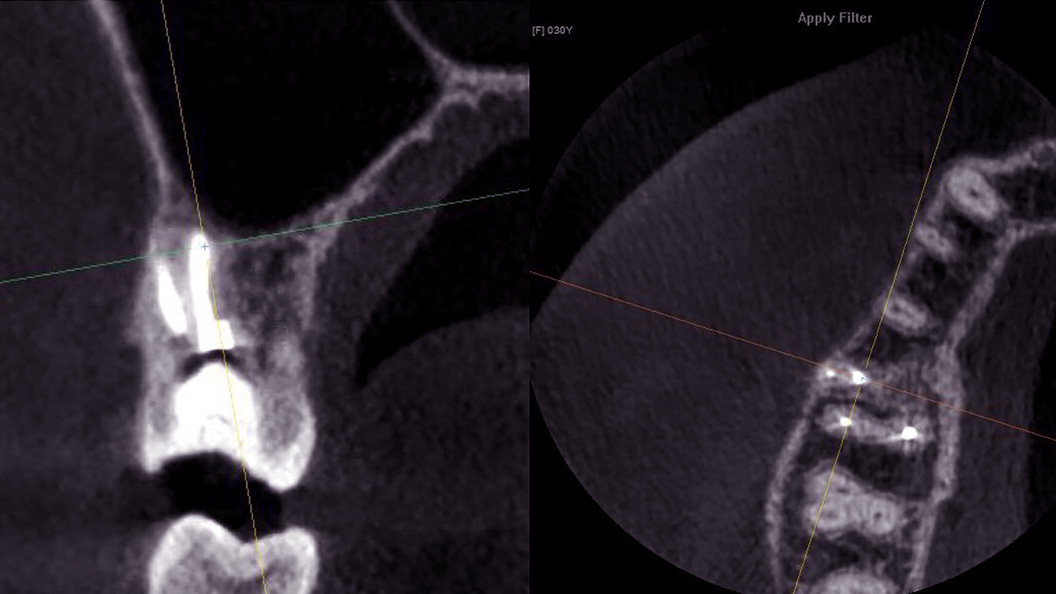

Пациентка после лечения в другой клинике обратилась в «Стоматологию Комфорта» с жалобами на ноющие боли в области жевательных зубов верхней челюсти. Боли усиливались при принятии пищи и горячих напитков. В результате проведения конусно-лучевой компьютерной томографии врач Вахлюева Елена Сергеевна обнаружила пропущенный дополнительный канал в ранее леченом моляре. Проведено селективное эндодонтическое лечение с пломбированием зуба.

- проведение конусно-лучевой компьютерной томографии и выявление проблемы;

- селективное эндодонтическое лечение зуба 1.6;

- пломбирование канала зуба.